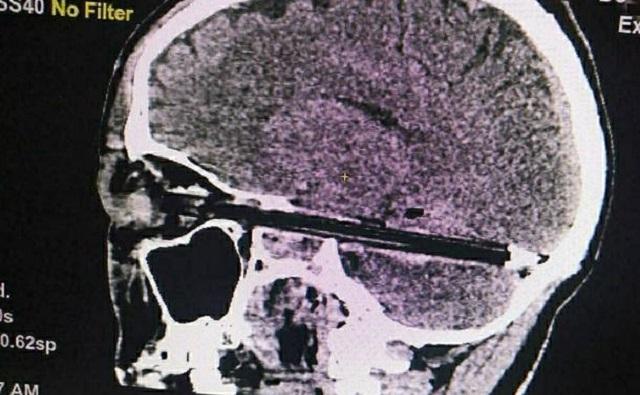

«В глаз ему вонзилась шариковая ручка, настолько, что, повредив глазное яблоко, вошла в мозг на весь диаметр полости черепа — от передней до задней черепных ямок», — говорилось в сообщении.

Пациента срочно прооперировали. Как выяснилось, ручка прошла всего в миллиметре от важнейших сосудов и ствола головного мозга. После извлечения инородного предмета мужчина был помещён в реанимацию. Вскоре он даже пришёл в сознание, однако утром 9 февраля умер.